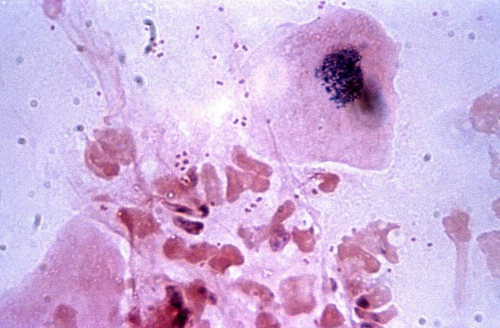

백혈구가 무엇인가?

백혈구는우리 몸을 건강상태를 유지하며 바이러스와 세균과 같이 외부물질로 인해 발생할 수 있는 질환들을 예방하며 면역 기능을 수행하는 중요한 역할을 한다고 합니다.

백혈구는 5개의 종류로 나누는데 림프구, 호중구, 호산구, 단구, 호염기구로 나누며, 백혈구의 정상적인 수치는 성인을 기준으로 보면 5000~11000개 정도라고 합니다. 이러한 수치보다 낮게 측정이 되게 되면 앞서 말한 5개의 종류 중에서 하나의 백혈구가 비정상적으로 낮아지게 되는 것이라 볼 수 있어요.